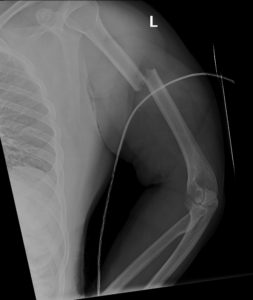

if the fracture is displaced, surgery may be needed to put the bone back into the correct position and fix the bone with Plates & screws or nails for adequate healing to occur.

- Humerus Fractures.